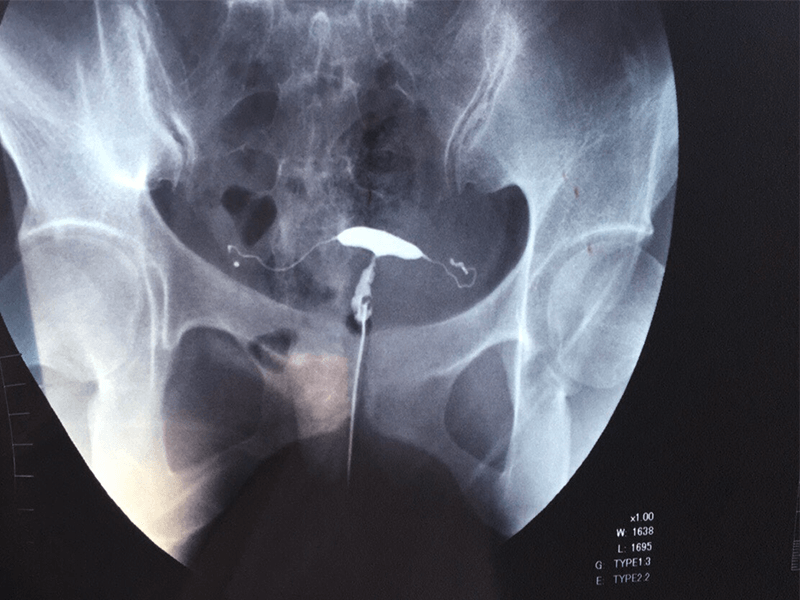

吃了一年中藥,終於鼓起勇氣去造了個影,因為去年造影的疼痛還記憶猶新,沒想到並沒有想象中的痛,而且雙側輸卵管都通暢了。我是被無數醫生判死亡令的那種,去年5月23日,第一次造影結果雙側輸卵管不完全梗阻,雙側傘端粘連梗阻、積水,右側傘端上舉,雙側輸卵管炎,子宮內膜炎。去了好幾家醫院醫生都說必須手術,中醫效果不大,僅一家以學術研究為主的中醫研究所告訴我中醫可以治,因為害怕手術,我最終選擇了中醫治療。拿到片...